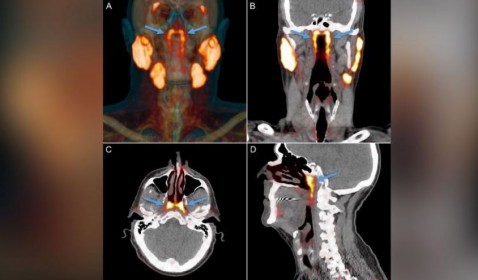

Descubren posible nuevo órgano en la garganta humana